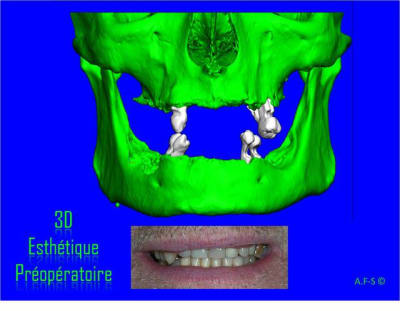

Projet implantaire:

Extraction, pose d’implants Ankylos, pose des piliers Standard définitifs, mise en charge immédiate bi-maxillaire en une chirurgie.

Maxillaire supérieur – extraction 13, 26, 7 implants en MCI, 1 implant en MCR pose summeurs, densification par ostéotme, comblement osseux, bridge provisoire sans fausse gencive avec renfort métallique.

Maxillaire inferieur – extraction 35, 34, 44, 45, 6 implants MCI, comblement osseux, bridge provisoire sans fausse gencive avec renfort métallique.

Le patient présente une perte de DV importante qui doit être corrigé avec les bridges provisoires.

3D

Esthétique

Préopératoire